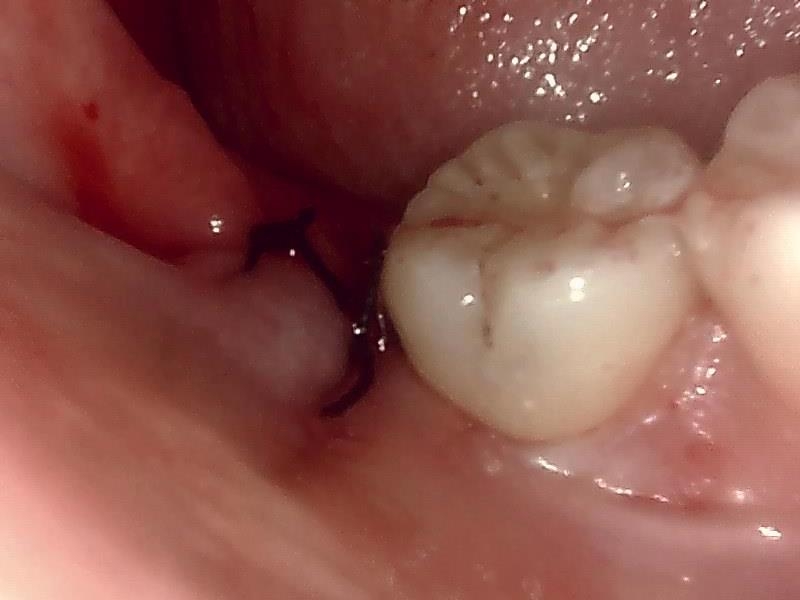

部位:右下8番埋伏歯

切開 歯肉剝離

歯肉を切開し、歯が見えるようにして、

周辺の骨を削らないように親知らずを分割し抜きやすくしていきます。

この抜歯法により術後の腫れ痛みが大幅に軽減されます。